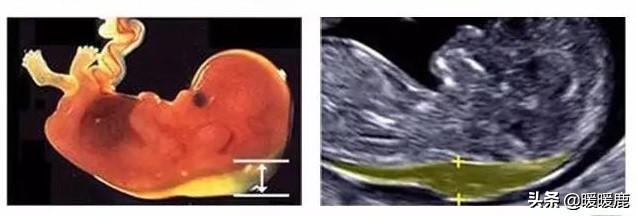

1、胎儿颈项部透明层(NT)

NT是“胎儿颈项部透明层”的英文缩写,是指胎宝宝颈背部的皮下积液厚度。孕妈一般会在孕11~13周做NT 检查时,如果NT值≥2.5mm 代表NT增厚,且NT越厚,胎儿患有染色体异常和畸形的几率越大,这时就要通过无创DNA或羊水穿刺进一步排查胎儿染色体异常的问题。另外还要结合孕中期的系统B超、四维彩超和胎儿心脏超声等检查,对胎儿进行全面评估。做了NT还要做唐筛吗?无创和羊水穿刺又是怎么回事?做了NT,还需要做无创DNA或羊水穿刺吗?

唐氏筛查NT